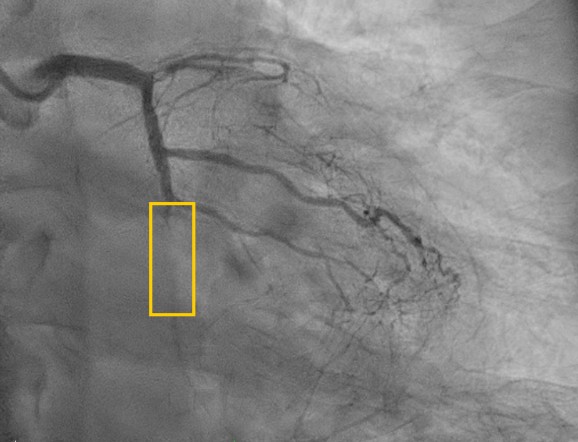

This time Left coronary angiography showed progression of LAD lesion (99% stenosis to total occlusion). We used Runthrough floppy to OM1 branch , then advanced Sasuke with XT-A via runthrough floppy for better support. For failure of passing through LCX distal lesion, we exchange XT-A to Gaia 2. Lesion was then crossed successfully then dilated with small balloons gradually (1.0 mm then 2.0 mm). We then confirmed with IVUS and showed the wire was in the true lumen.